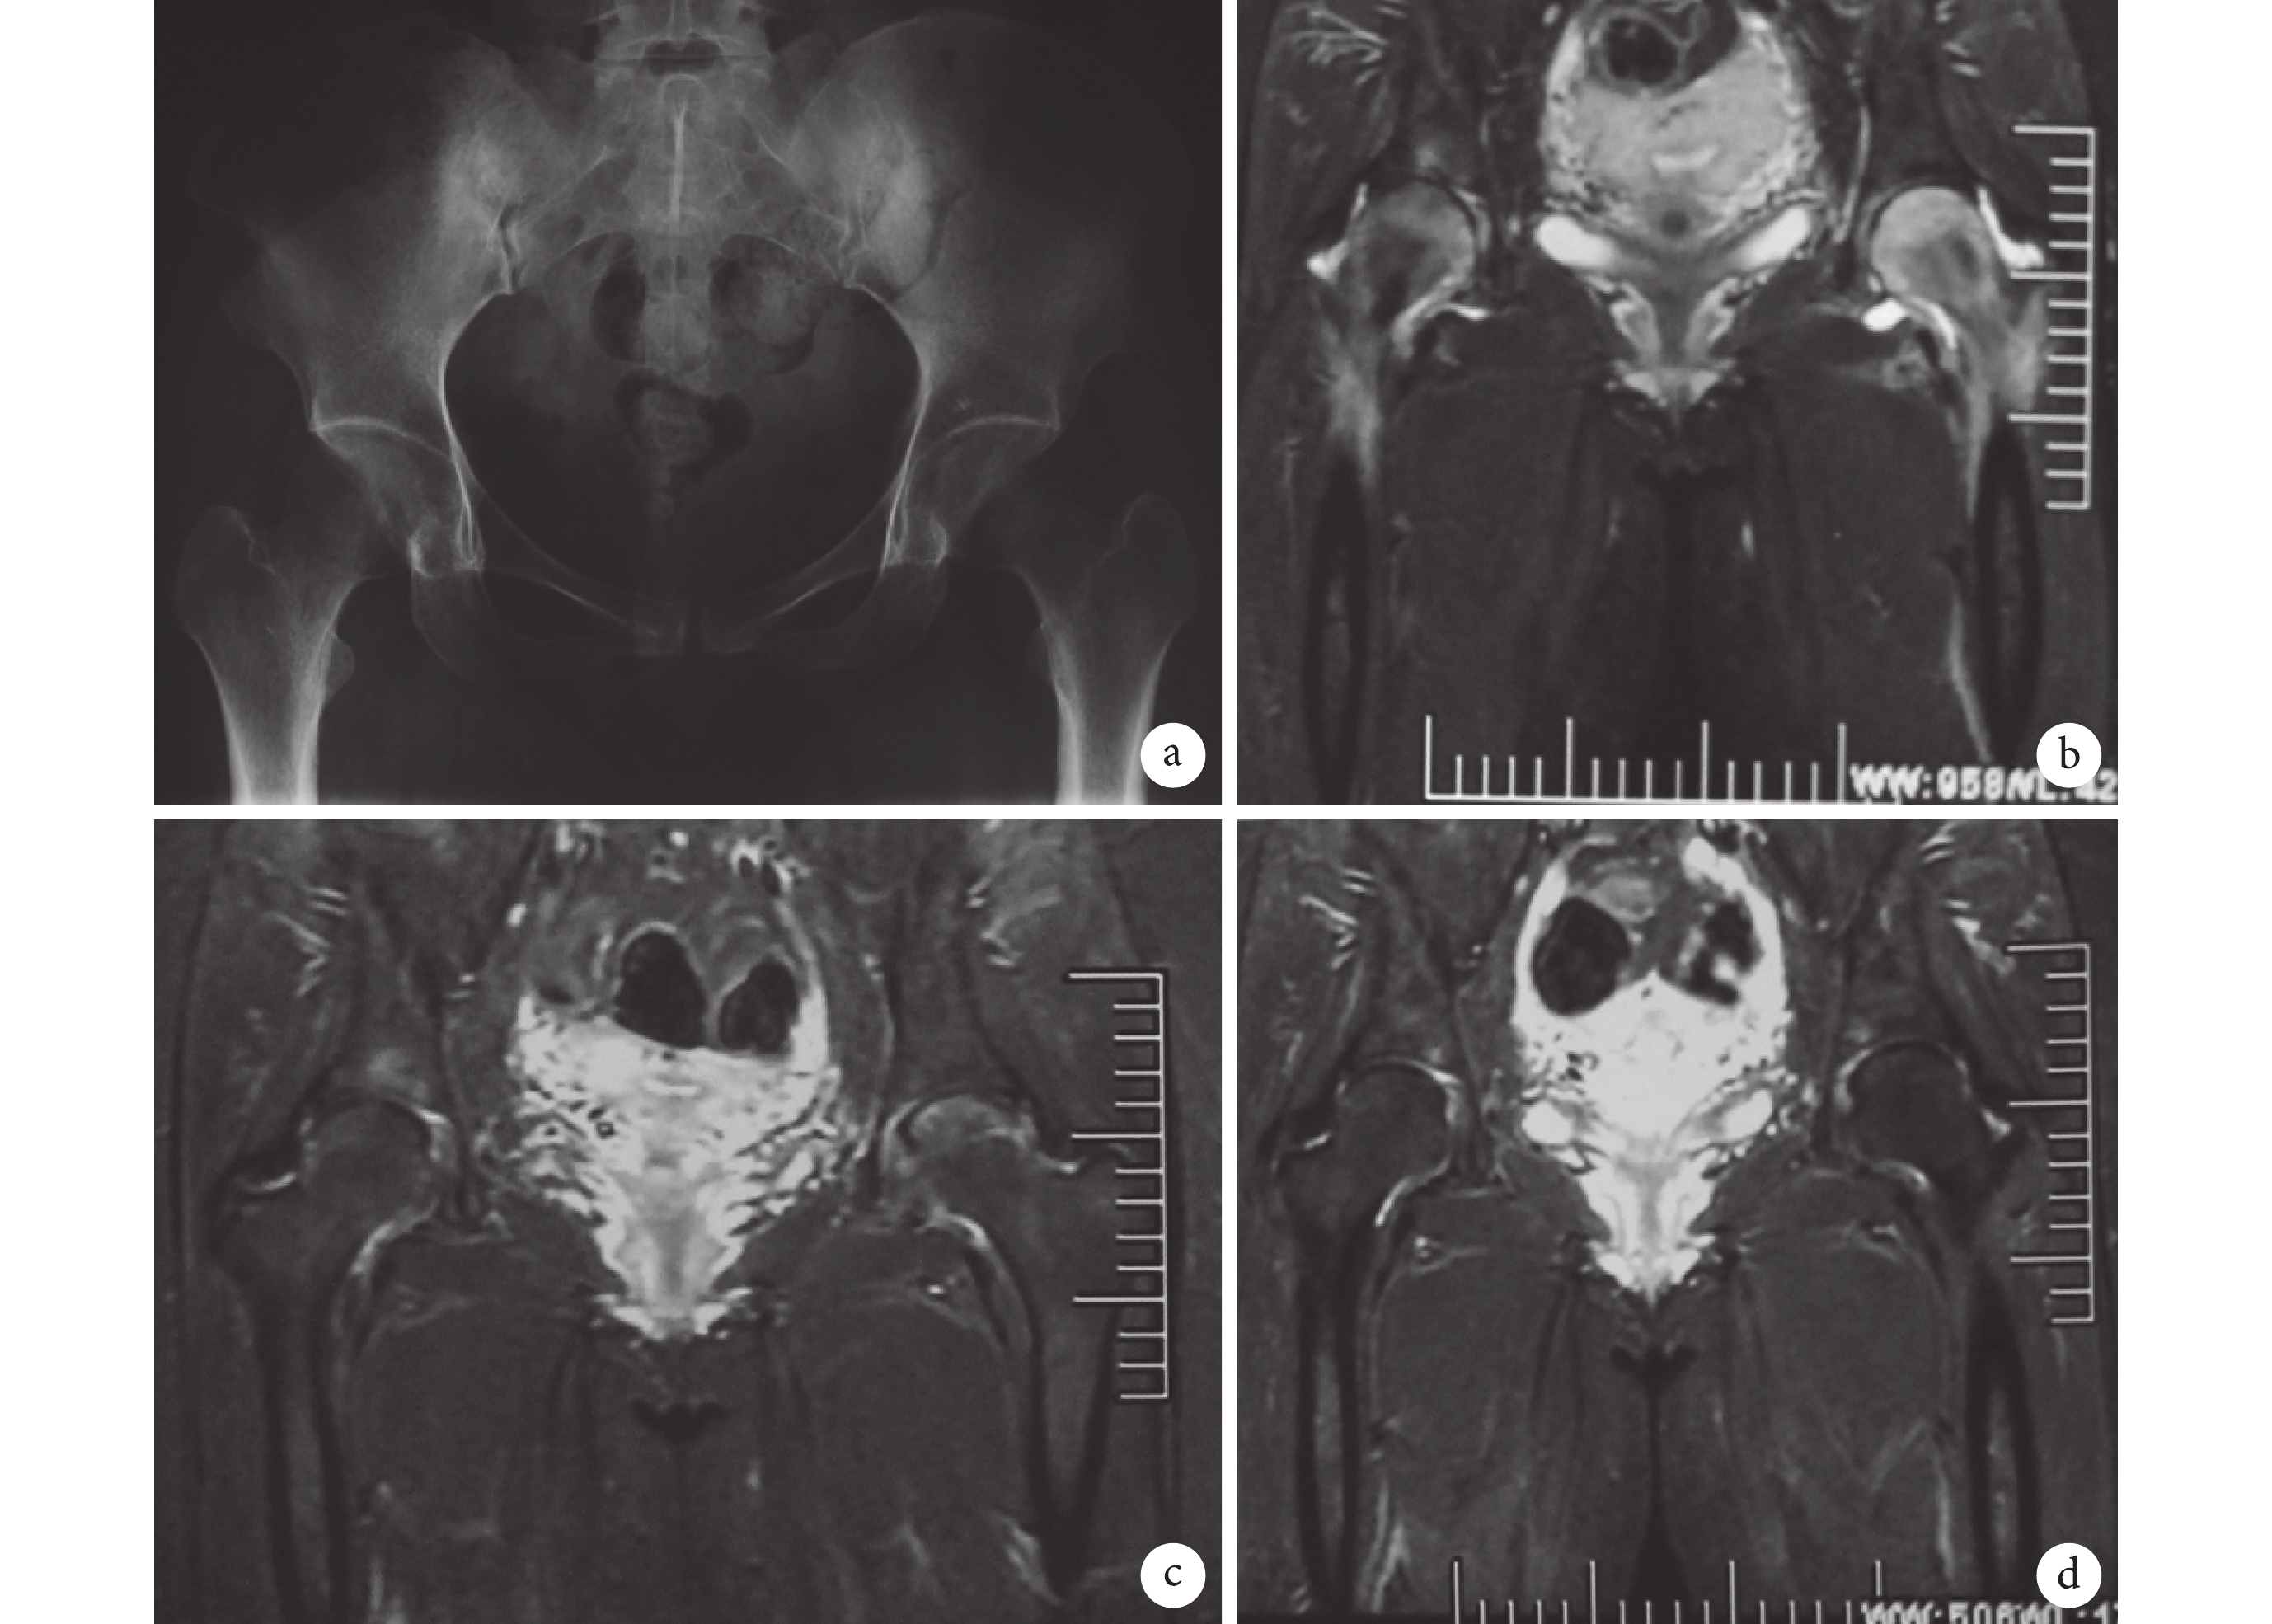

所有患者均獲得完整隨訪資料,隨訪時間 3~12 個月,平均(5.2±1.2)個月。8 例患者(10 個患髖)中共有 7 例(9 個患髖)獲得臨床治愈,治愈率 90%。臨床治愈患者啟動治療到臨床治愈的治療時間為 1~2 個月,平均(1.7±0.2)個月;從患者出現臨床癥狀到臨床治愈的時間為 2~8 個月,平均(4.7±1.4)個月;髖關節 Harris 評分由治療前平均(57.8±6.3)分提升到最后(98.6±1.0)分,差異有統計學意義(t=18.299,P<0.001)。典型患者治療前后髖部影像圖見圖 1。

a. 啟動治療前骨盆 X 線片未見明顯異常;b. 治療前 MRI 檢查示雙側股骨頭頸及轉子間區大量水腫(Ⅲ級);c. 治療 1 個月復查髖關節 MRI,示水腫明顯消退,尚未完全消失;d. 治療 2 個月復查髖關節 MRI,示水腫完全消退。患者,女,32 歲,產后 4 個月無明顯誘因出現雙髖關節疼痛,患者從發病到治愈病程為 2.5 個月